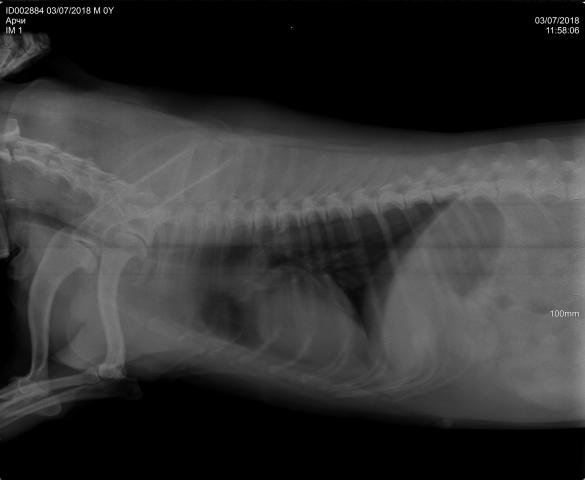

Размет передних лап

Я, конечно, не ветврач, но думаю это состояние как-то связано с суставами, может врожденное или вследствие нехватки кальция. Для уточнения диагноза придется обратиться к врачу.

Причин размета лап может быть несколько. Как вы нагружаете свою собаку? Причина может быть в повешенных или пониженных нагрузках. Вы держите собаку дома или на улице? Если собака домашняя, то причиной часто служит скользкое напольное покрытие(ламинат), собаке необходимо ходить по песку, щебню. Так же необходим анализ крови на витамины и кальций-фосфорное отношение. Какой рацион кормления у вашего щенка? Хватает ли ему минеральных веществ и витаминов для развития костной ткани суставов. Необходимо включит в рацион мясо-костную муку, рубец и субпродукты, рыбную муку, творог.